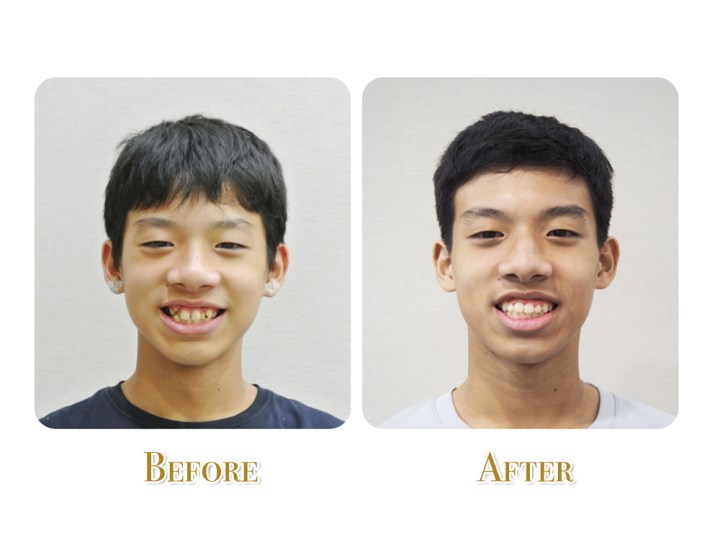

可愛的美眉治療前後 (正面照)

終於拆矯正器了!

這位可愛的美眉,ㄧ開始來找黃醫師的時候、愁眉苦臉的,詢問之下,因為北上來求學的關係,原本在自己家鄉做的牙齒矯正好一陣子沒什麼進展。